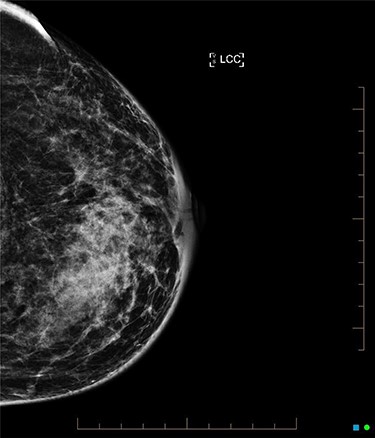

An ultrasound of the left breast demonstrated a 60-mm irregularity with no underlying collection at the 10 O’clock position, 2 cm from the nipple (Fig. 1). AB was treated with 5 days of oral flucloxacillin for presumed mastitis, and underwent a bilateral mammogram and ultrasound due to the suspicious irregularity of the left breast lesion. This showed an area of asymmetric density in the medial left breast with hyperemia (Fig. 2). The right breast showed two clusters of pleomorphic microcalcifications in the upper outer quadrant, further characterized as irregular lesions measuring 16 × 11 × 11 mm and 9 × 10 × 7 mm (Fig. 3).

Core biopsy of the right breast demonstrated a high-grade ductal carcinoma in situ (DCIS) (Fig. 4), whilst staging computed tomography and bone scan showed no evidence of distal disease. Magnetic resonance imaging (MRI) identified a resectable 60-mm area in the right outer quadrant. AB underwent an oncoplastic right wide local excision with sentinel lymph node biopsy (SLNB), subsequently requiring an axillary dissection due to macrometastatic axillary disease. Histopathology showed multifocal high-grade invasive ductal carcinoma with immunotyping of Grade 3, PR ++, HER-2 negative, resulting in an adjuvant chemotherapy regime of cyclophosphamide and doxorubicin. The left breast was monitored without change during this time. Fully fractionated whole breast radiotherapy with boost to the tumor bed and regional lymph nodes is scheduled, alongside risk reducing endocrine therapy.